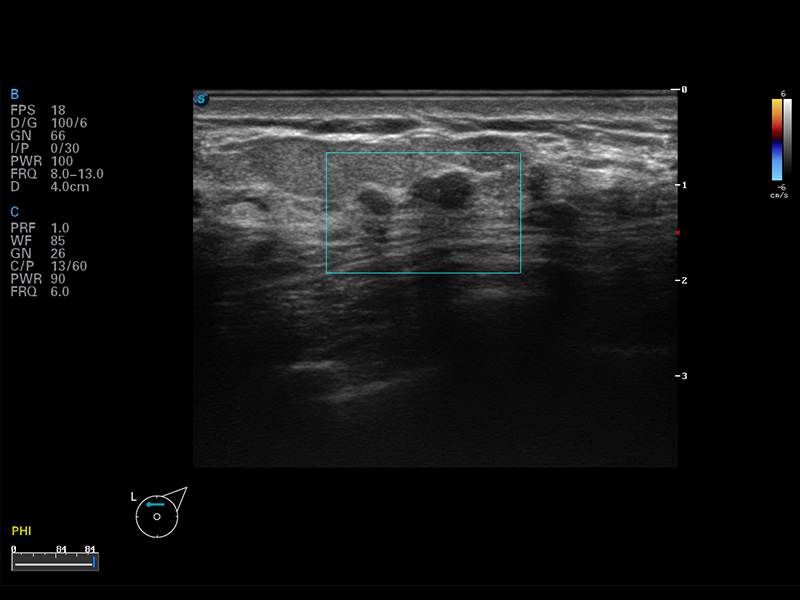

S8 EXP便携式彩色多普勒超声诊断仪是米兰官方网站研发的高端全身应用型便携彩超。高通道的VIS平台融合可视化(Visual)、智能化(Intelligent)和人性化(Smart)的特点,配以米兰官方网站自主研发生产的探头大家族,使您能够快速、准确的获得病人信息,提高工作效率的同时减轻疲劳。

μ-Scan微米成像

谐波成像

空间复合成像